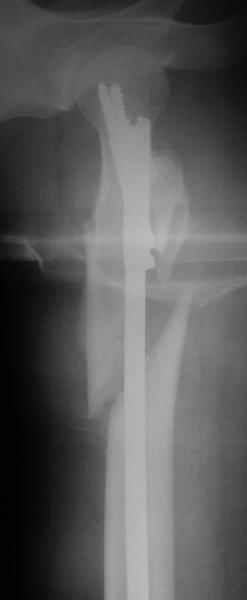

Другое наблюдение:Мужчина, 1957 г.р. Травма в результате ДТП 12.09.04г.

Диагноз: Закрытый оскольчатый подвертельный перелом правой бедренной кости со смещением отломков, оскольчатый перелом большого вертела, отрывной перелом малого вертела.Сопутствующие заболевания: Язвенная болезнь желудка, ремиссия.

Наверно, можно и так сказать, но можно и тоже самое - 4-фрагментный вертельный перелом. Выбор тот же, но с учетом молодого возраста реконструкционный гвоздь тут более применим. Вот уже наш пример.